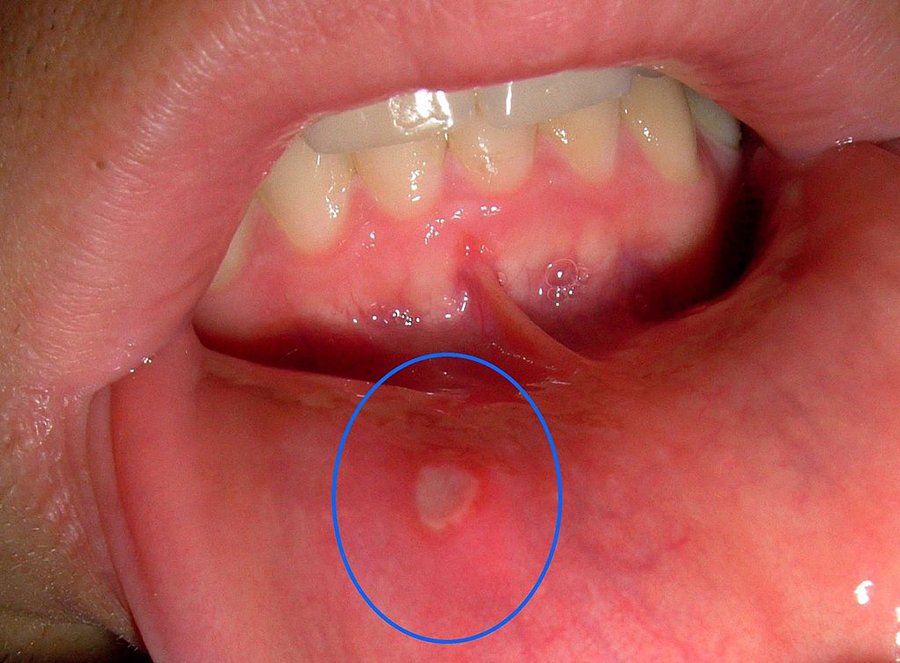

อาการร้อนใน เป็นอาการที่ส่วนใหญ่มักเกิดขึ้นเมื่อร่างกายมีอุณหภูมิสูง หรือสะสมความร้อนมากเกินไป จนทำให้ร่างกายแสดงความผิดปกติต่างๆ ออกมา ไม่ว่าจะเป็นแผลในช่องปาก ลิ้น หรือกระพุ้งแก้ม มีอาการเจ็บคอ หรือท้องเสีย เป็นไข้ รู้สึกไม่สบายร่วมด้วย ซึ่งอาการก็จะแตกต่างกันออกไปตามร่ายกายของเรา ด้วยอาการที่ร่างกายแสดงออกมานี้ ทำให้การดำเนินชีวิตประจำวัน มีอุปสรรคมากขึ้น เช่นการเป็นแผลร้อนในในช่องปาก จะส่งผลให้เมื่อรับประทานอาหารลำบาก รู้สึกแสบร้อนในบริเวณแผล มีอาการเจ็บคอ กลืนอาหารลำบาก หรือเป็นไข้ ไม่สบาย เป็นต้น